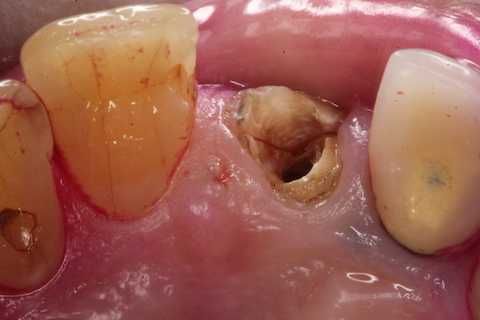

左下7遠心カリエスと8番抜歯 2025.07.29